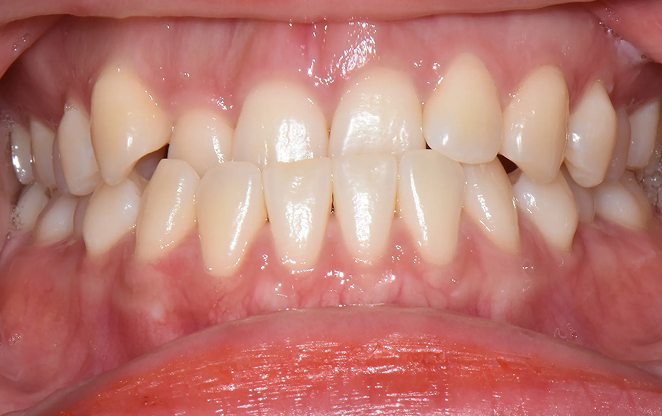

초등학생 1차 교정은 영구치가 나오기 전 혼합치열기에 시작하는

교정입니다. 이 중요한 시기에 치아가 제대로 자리 잡을 수 있도록,

아이의 밝은 미래를 위한 준비를 도와드릴게요.

Before

After